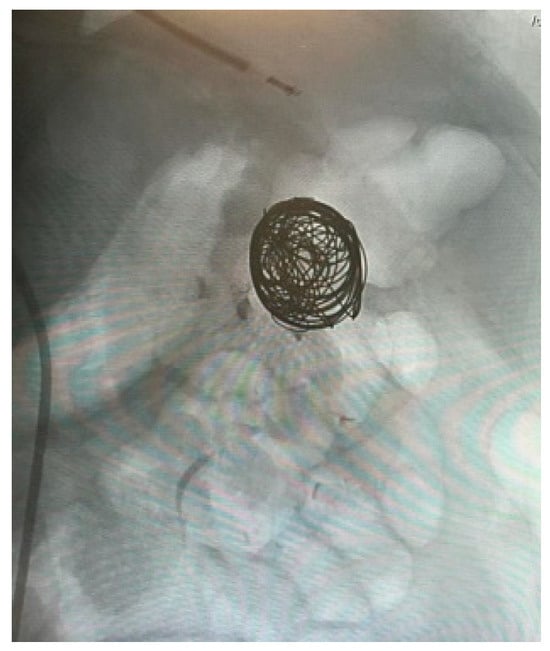

Appendix A.3. Clinical Case 3: Splenic Visceral Aneurysm